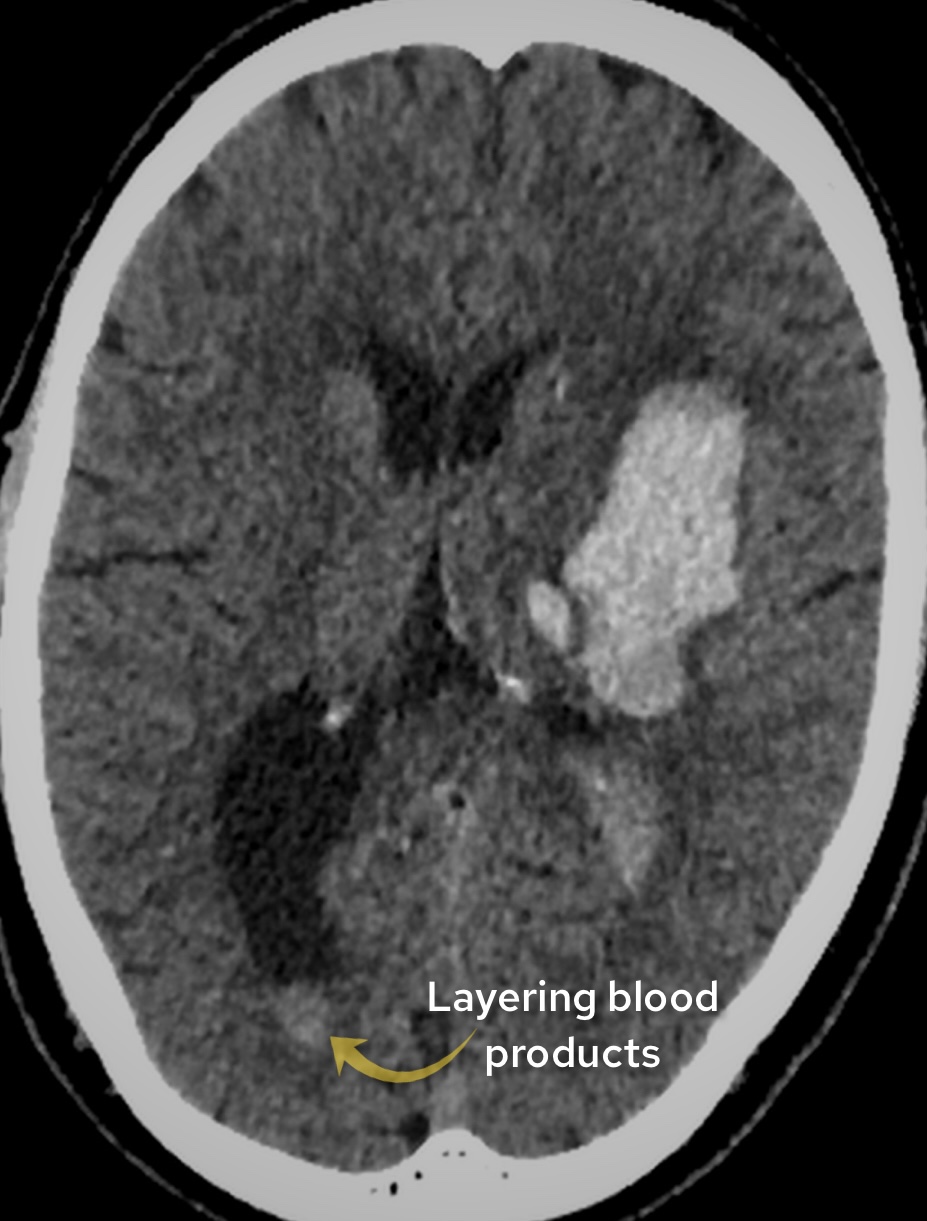

Case 2

A male in his 70s presents with right sided weakness. Have a look at this image from a non contrast CT head. What best describes the finding and most likely diagnosis?

Choose from one of the following options: